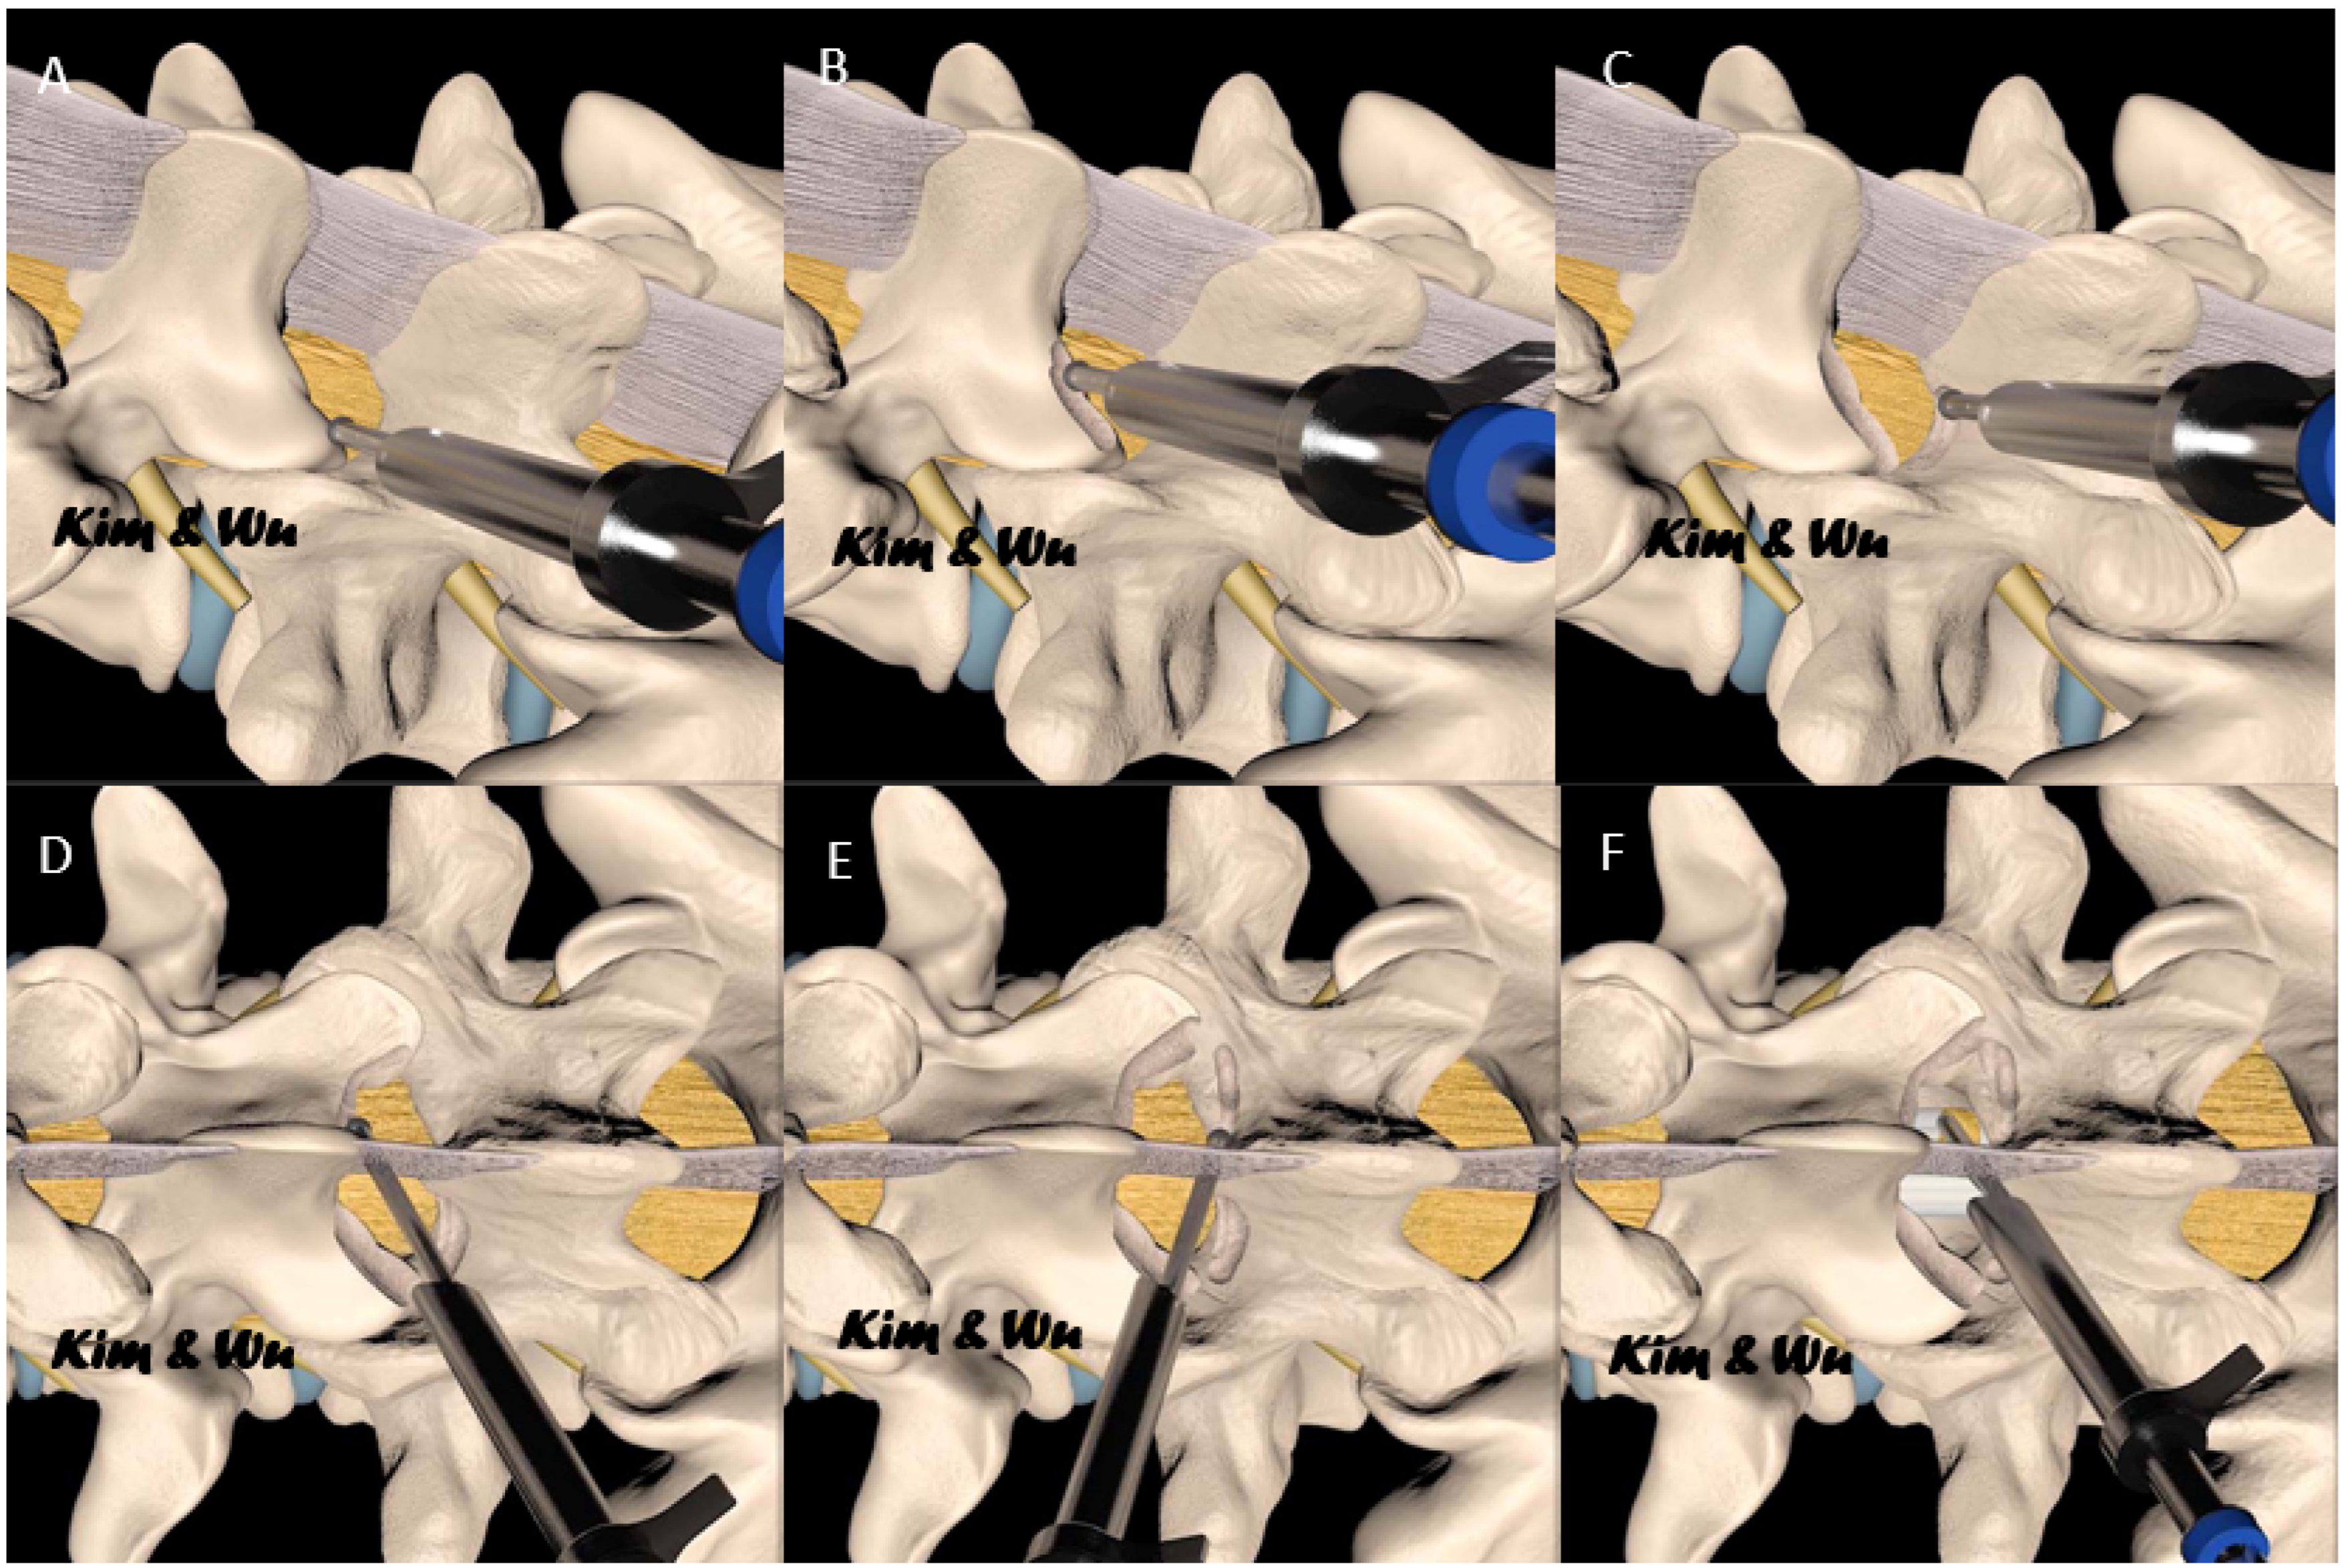

2.2. Surgical Technique of Lumbar Endoscopic Unilateral Laminotomy with Bilateral Decompression and Interlaminar Contralateral Endoscopic Lumbar Foraminotomy

- Kim, H.-S.; Wu, P.H.; Jang, I.-T. Lumbar Endoscopic Unilateral Laminotomy for Bilateral Decompression Outside-In Approach: A Proctorship Guideline With 12 Steps of Effectiveness and Safety. Neurospine 2020, 17 (Suppl. 1), S99–S109. [Google Scholar] [CrossRef] [PubMed]